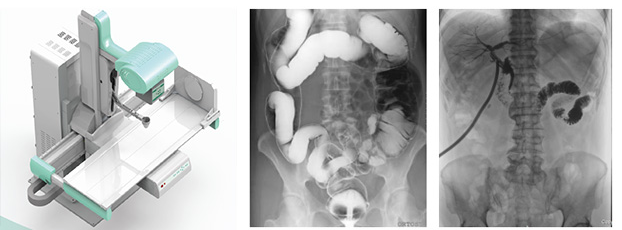

目前,普放型X射線設備領域前沿產品——動態(tài)DR已經廣泛應用于臨床影像診斷。但目前市場上也有一些類似的產品,在影像診斷上相比以前的設備都有了較大的進步,但和真正意義上的動態(tài)DR依舊有一定的差距。那么,作為消費者的我們應該怎樣才能購買到真正的動態(tài)DR?下面小編就給大家說5點,讓大家可以作為參考去進行購買,一起來了解一下吧!

1、真正的動態(tài)DR只有一個探測器

2、無需影像增強器

真正的動態(tài)DR是不用影像增強器的。雖然影像增強器在醫(yī)學影像史上有重要的歷史地位,但是隨著科學技術的日益革新,目前動態(tài)DR探測器在影像的各個領域都墊付了影像增強器的功能。

3、成像視野是17英寸方形而非7/9/12英寸圓形

目前DR的成像面積都是17英寸×17英寸方形成像,這在臨床應用中有巨大的優(yōu)勢。

4、動態(tài)成像像素100萬以上,動態(tài)點片像素900萬以上

5、毫秒級動靜切換實時成像